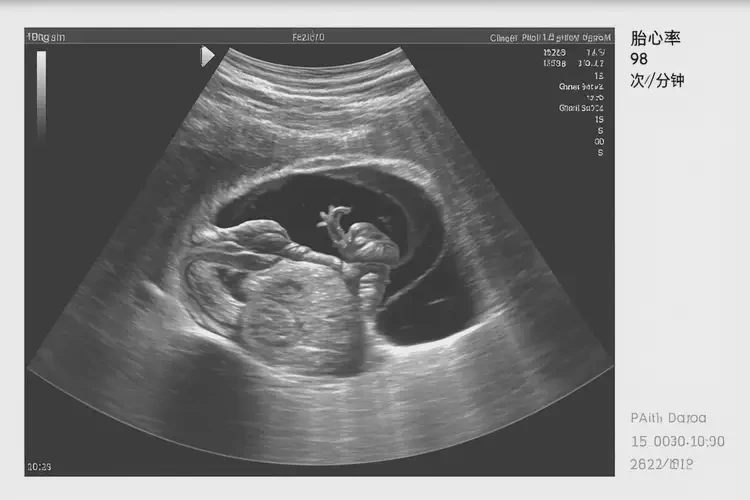

孕12周1天胎心96正常嗎

胎心96次/分鐘在孕12周1天可能偏低。通常情況下,孕12周的胎兒心率應(yīng)在120-160次/分鐘之間。胎心率受多種因素影響,包括胎兒活動、母體狀態(tài)等,因此一次測量結(jié)果并不能完全反映胎兒健康狀況。

孕12周1天胎心96正常嗎(圖1)

孕12周1天胎心96正常嗎(圖2)

孕12周1天胎心96正常嗎(圖3)

孕12周1天胎心96正常嗎(圖4)